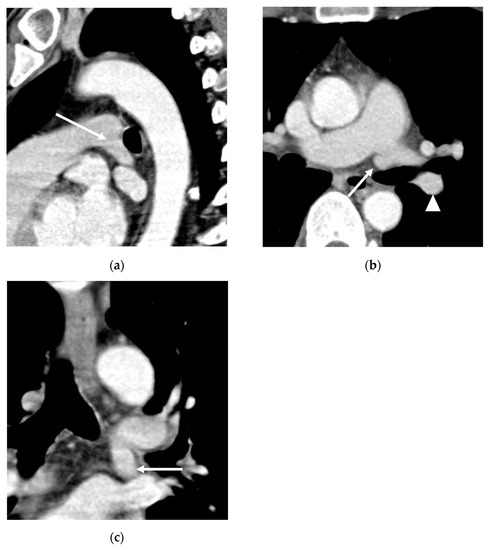

3. Results

3.2. Lobar and Segmental Supply Patternf of the AP

3.3. Diameter of the AP

3.4. Presence of Other Accompanying Variations

4. Discussion